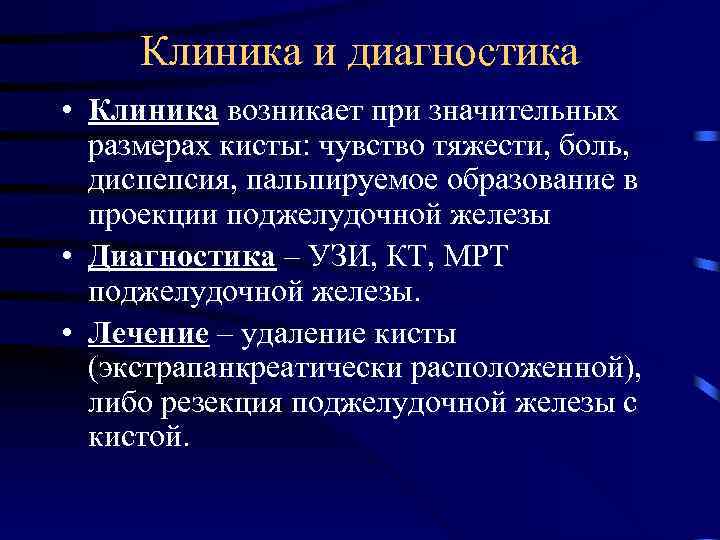

Клиника и диагностика • Клиника возникает при значительных размерах кисты: чувство тяжести, боль, диспепсия, пальпируемое образование в проекции поджелудочной железы • Диагностика – УЗИ, КТ, МРТ поджелудочной железы. • Лечение – удаление кисты (экстрапанкреатически расположенной), либо резекция поджелудочной железы с кистой.